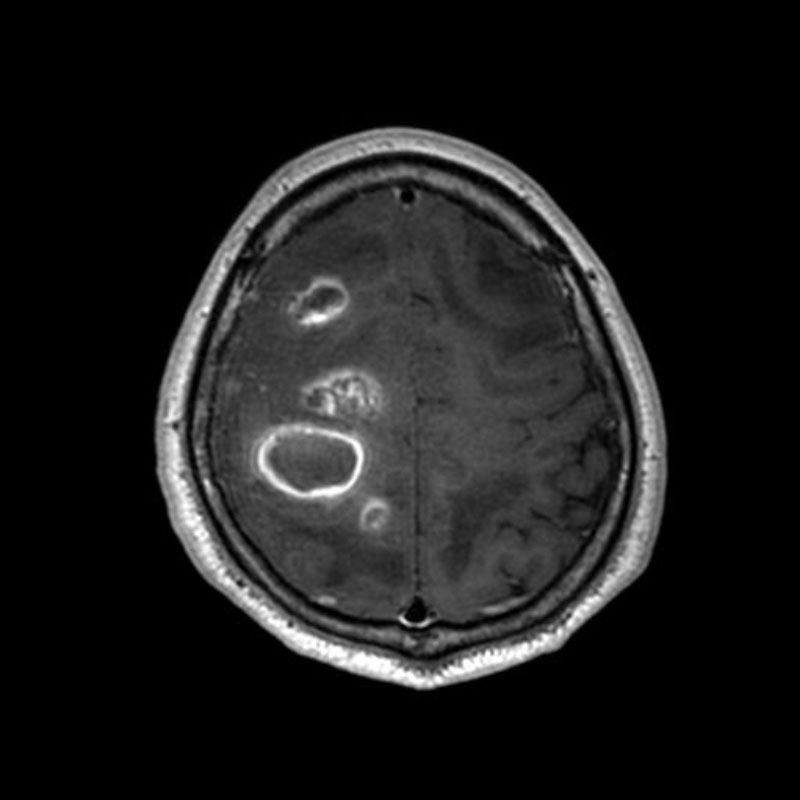

619

'25年4月

60代

脳腫瘍

頭蓋内腫瘍摘出術

No.’25_21 手術前1

No.’25_21 手術前2